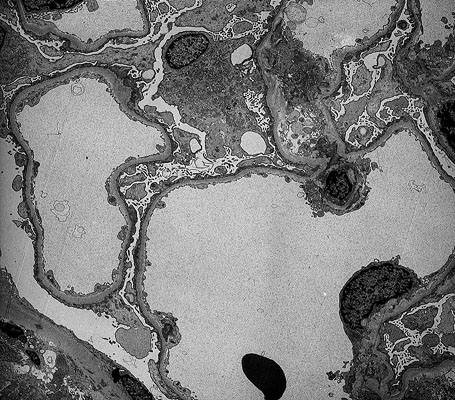

Minimal change nephrotic syndrome, EM

Electron micrograph - two glomerular capillaries and parts of a few others are present, the injury to the epithelial cells is manifest morphologically by effacement of foot processes.